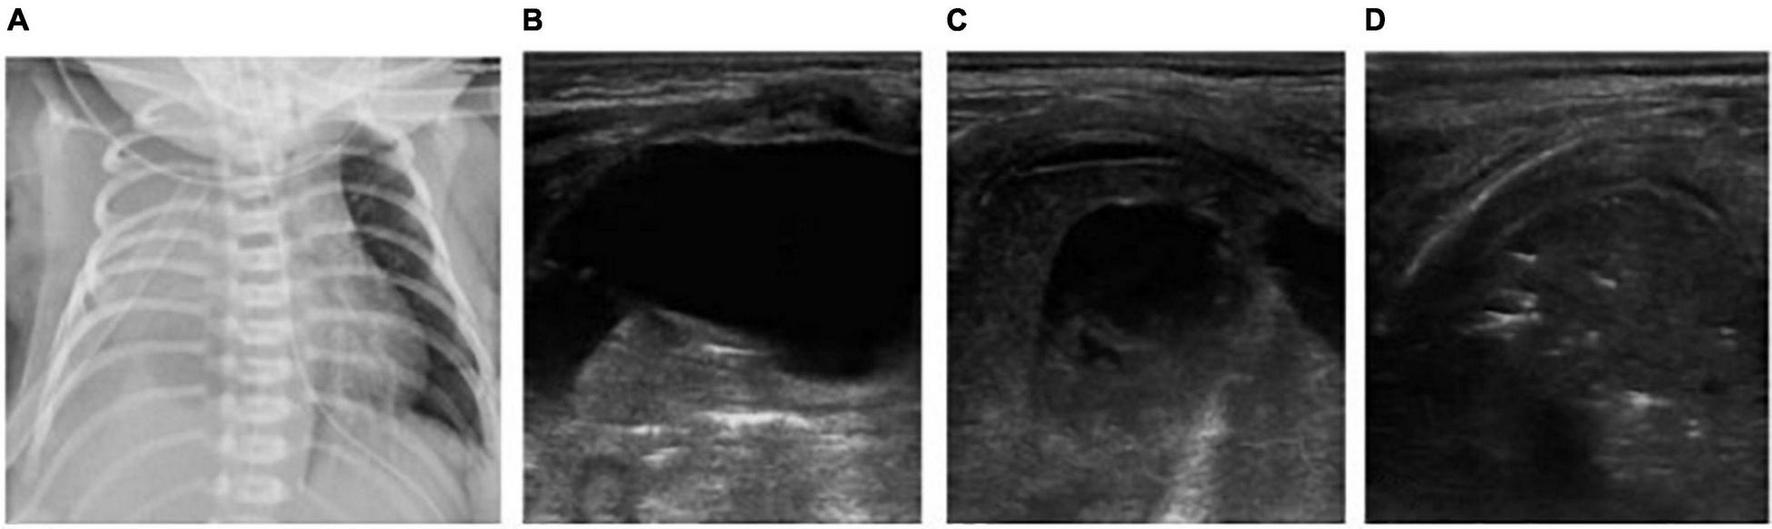

FIGURE 1

The neonate was born at 36 weeks of gestational age by Cesarean section due to the mother’s central placenta previa hemorrhage. The amniotic fluid was clear, and the Apgar score of 1, 5, and 10 min of birth were 10 points. The neonate had labored breathing and shortness of breath 10 min after delivery and mechanical ventilation was required. It was diagnosed as severe wet lung. (A) Chest X-ray: Lung permeability decreases, and the white lung changes. (B,C) Ultrasound findings: Rough pleural line, reduced A-line, alveolar interstitial syndrome (AIS), double lung points but no consolidation, which conforms to the ultrasonic characteristics of wet lung. After 24 h of treatment, the neonate’s breathing improved. LUS showed that B-lines was significantly reduced and the patient was successfully evacuated from the ventilator. The clinical outcome was consistent with the characteristics of wet lung.

FIGURE 2

The patient is a twin neonate born at 32 weeks of gestational age by Cesarean section due to “fetal distress” with clear amniotic fluid and the Apgar score of 1, 5, and 10 min of birth were 5, 7, and 7 points. After delivery, the neonate had cyanosis, labored breathing, and severe pulmonary hypertension, and high-frequency ventilation was performed. It was diagnosed as neonatal respiratory distress syndrome (RDS). (D) Chest X-ray: White lung changes. (A–C) LUS: Abnormal pleural line, the disappearance of A-lines, white lung change, snowflake sign, such as air bronchogram visible below pleura, which conforms to the ultrasonic characteristics of severe RDS.